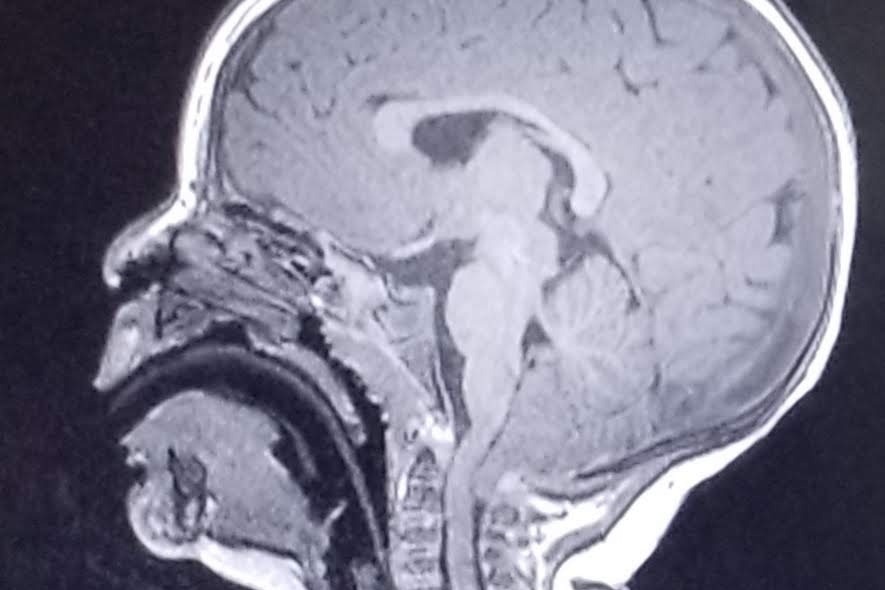

Our sweet little “Araya Love” lights up a room with smiles everywhere she goes! People are smitten by her joy and happiness! This is even amidst her constant pain and struggles. Araya's prognosis is Rett Syndrome, as we continue to wait for genetic blood work to help officially diagnose. Currently, Araya has been diagnosed with Chiari 1 Malformation in her brain, dystonia, chorea, movement disorder, failure to thrive, sleep disturbances, breathing abnormalities and severe acid reflux.